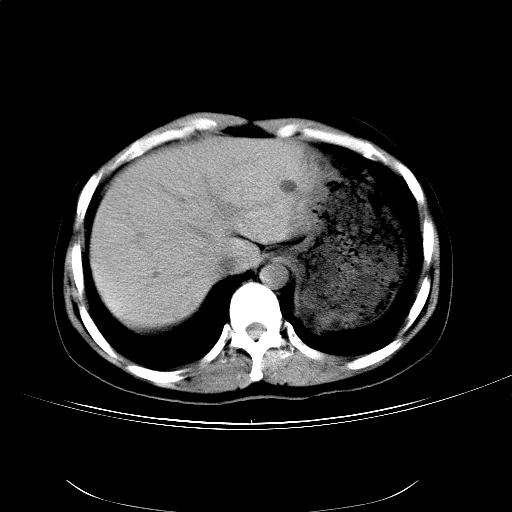

女,36岁,右上腹不适数天。5天后公布结果。

肝左叶有俩原形低密度,边缘光整,内密度均匀一致,考虑小囊肿。

右侧肾上腺区域不规则低密度占位性病变,似乎有俩病灶不完全相连。密度不均匀,内见钙化。首先考虑囊肿,建议增强薄层扫描。

支持1肝内小低密度灶考虑多系囊肿。2右侧肾上腺区低密度结节影,其内见两个小点状钙化灶,低密度影似有分叶或为两个,右肾上部显示不清。考虑右侧肾上腺良性占位病变,请结合临床及超声与增强检查。

比较典型的右侧肾上腺囊肿;肝脏左外叶上段小囊肿。

结果:肾上腺囊肿。